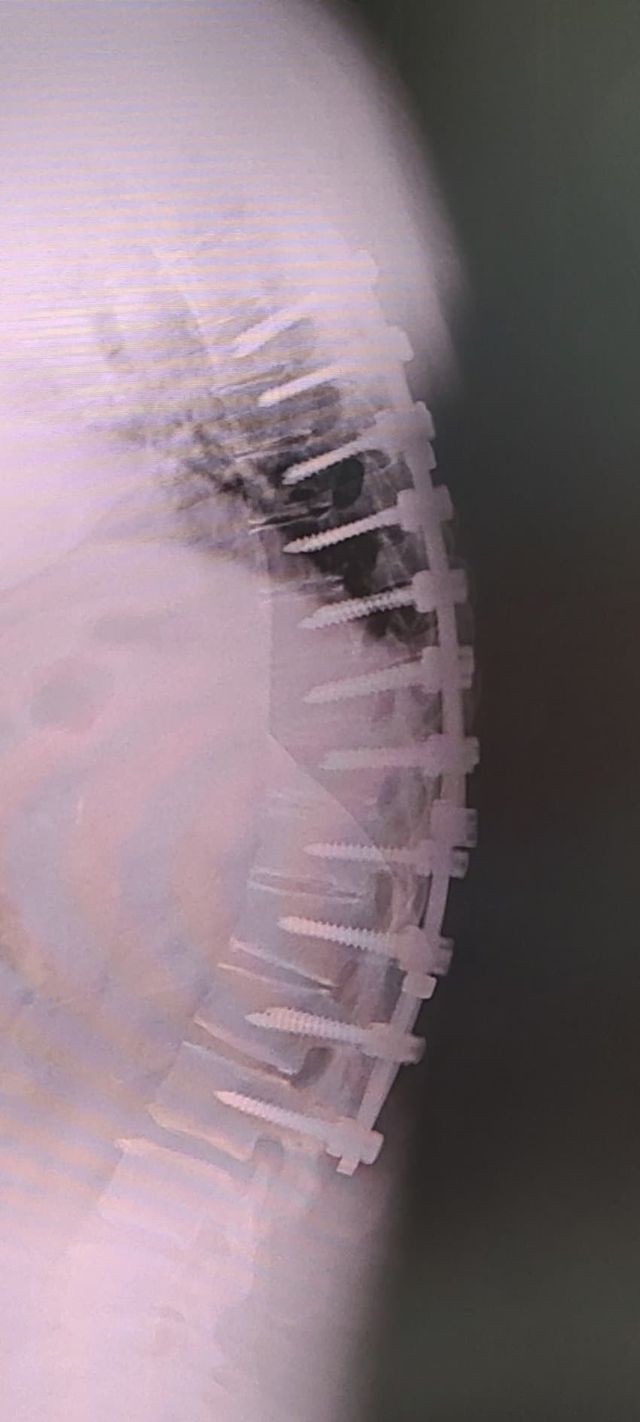

나 12사에서 죽을뻔하고 척추에 심 21개 박은 사람이다

[시리즈] 티타늄맨 이야기

나도 12사때 훈련병시절 완전 군장하고 쓰러지고

척추 무너지고 희귀병 진단받아서

12사 내 의무사단에서 핵고통 받다가 죽다살아난 사람이다

척추 심 21개

척추에 심 21개를 박는 것은 매우 심각한 의료적 조치입니다. 이는 대규모의 수술과 회복 과정을 필요로 하며, 환자의 삶에 큰 영향을 미칠 수 있습니다. 척추 수술이나 시술에 대한 정보와 경험을 나누는 것은 많은 사람들에게 유용한 자료가 됩니다.